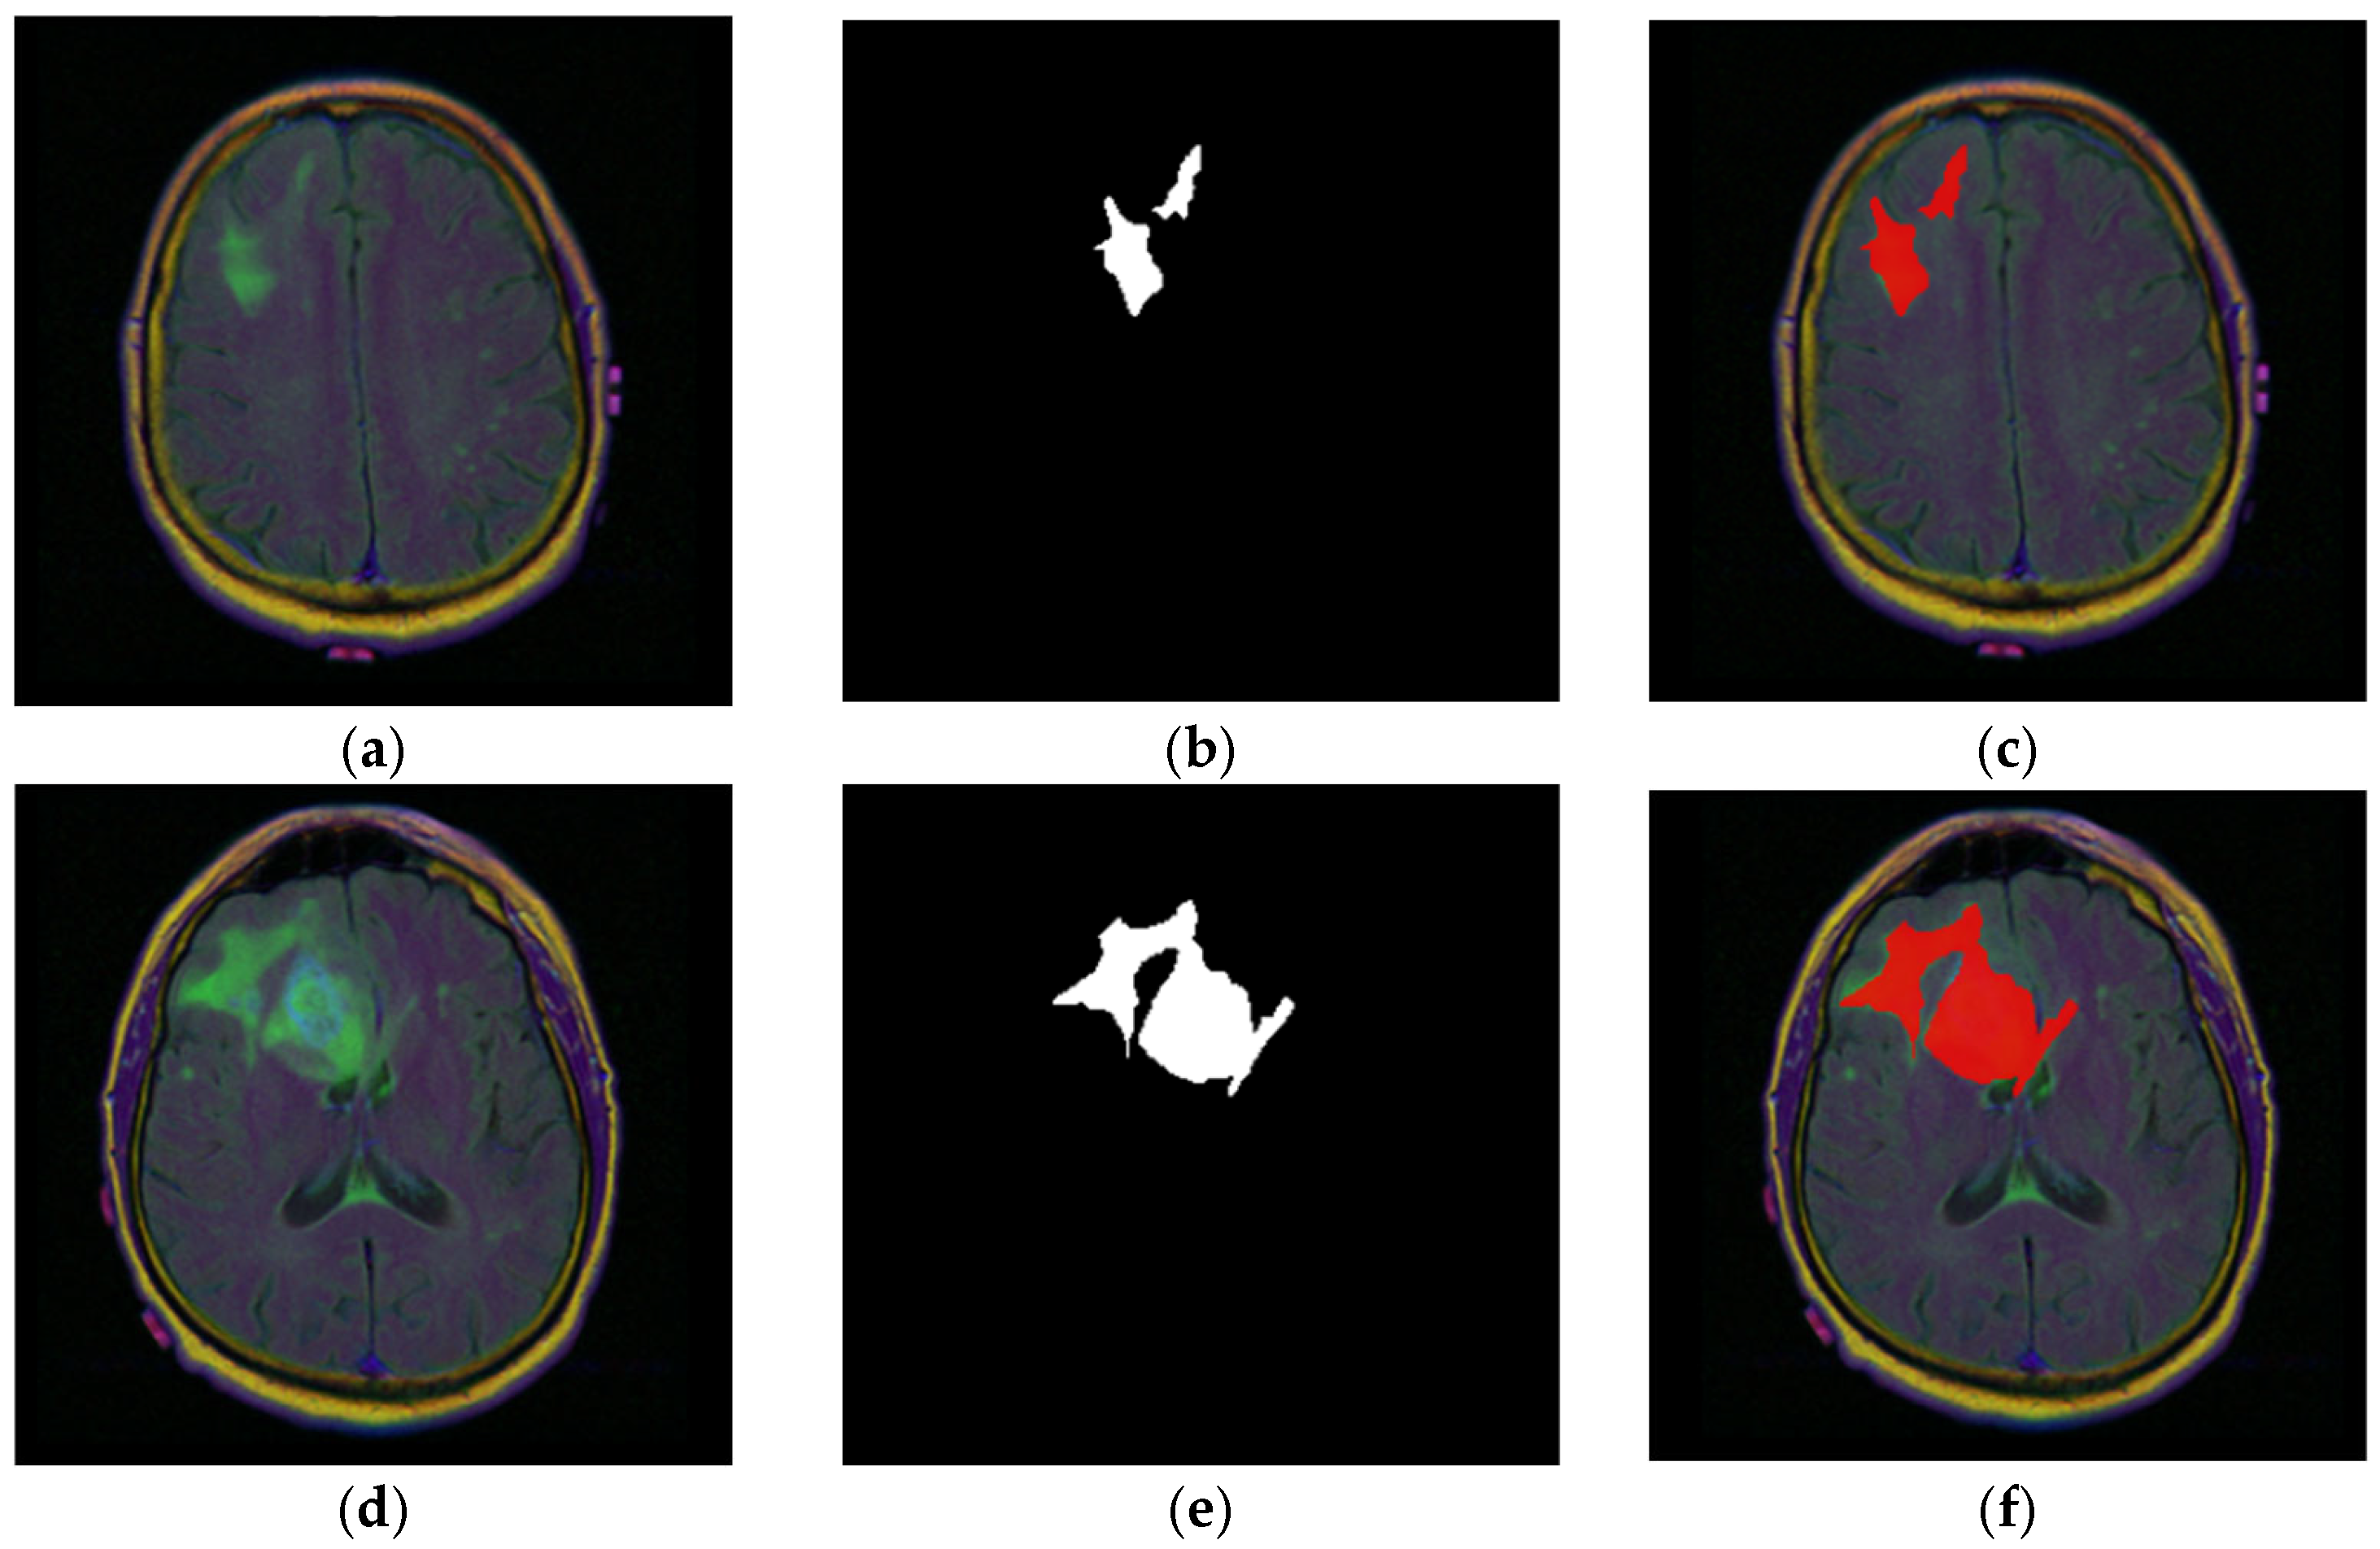

3.1.2. Dataset Visualization

4.2. Qualitative Results